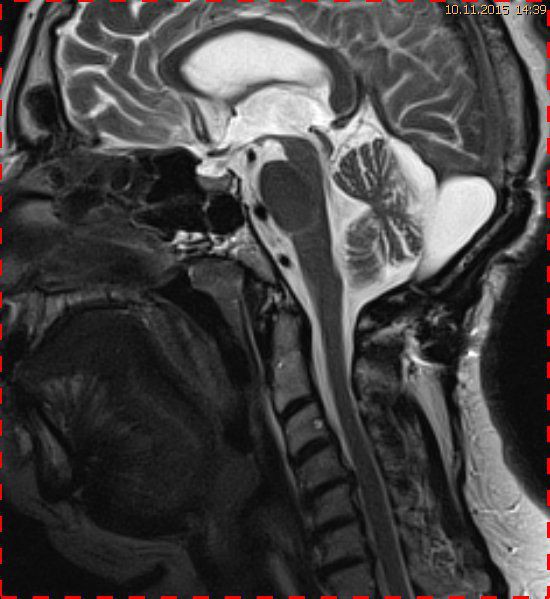

Abb. 2.1 Sagittales MRT (T2 TSE, 1,5 T): bei unveränderter Streckfehlhaltung der HWS 2 Monate nach der Erstuntersuchung Progredienz des Tonsillentiefstands, Syringomyelie

Trotz weiterer Schmerz- und Physiotherapie konnte keine Beschwerdereduktion erreicht werden. 2 Monate später erfolgte eine MRT des Kopfes zum Ausschluss einer posttraumatischen Veränderung.

Bei dieser Untersuchung wurde übersehen, dass die Kleinhirntonsillen in das Foramen magnum disloziert waren und eine Arnold-Chiari-Malformation mit Erweiterung des 4. Ventrikels und des Aquäduktes inklusive Kleinhirntonsillentiefstand vorlag. Bei zwischenzeitlich auswärtig erfolgtem CT der HWS wurde eine Anlagestörung im kraniozervikalen Übergang beschrieben. Eine Kontrolluntersuchung des Kopfes weitere 4 Monate später dokumentierte neben einem medullären Ödem einen progredienten Tonsillentiefstand, der zur neurochirurgischen Behandlung mit operativer Erweiterung des Foramen magnum führte.